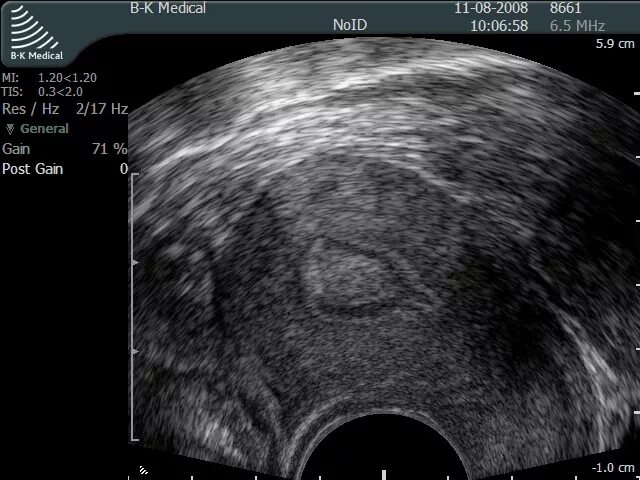

Что такое кисты эндоцервикса шейки матки